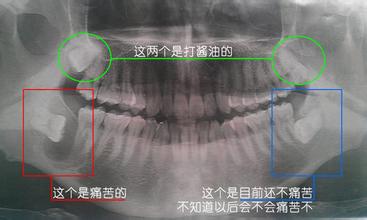

建議有拔牙需求的朋友到醫院檢查一下,拍個(ge) 牙片,看您的智齒位置及牙根的情況,醫生會(hui) 根據具體(ti) 情況給您治療建議。>>>點擊谘詢:拍牙片多少錢<<<